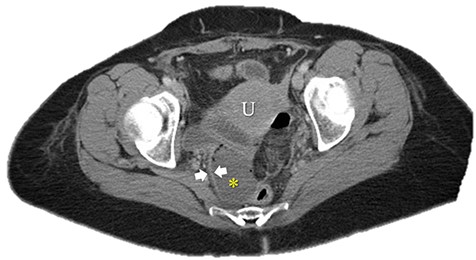

Immediate postoperative course was uneventful until postoperative day (POD)-5 when she experienced multiple watery stools, diffuse abdominal pain, fever (102.6F) and leukocytosis (23000/UL). Clostridium difficile infection was ruled out with a negative stool toxin assay. Her abdominal exam remained nonspecific until POD-6 when she had bilious emesis. A computed tomography (CT) scan revealed perforated diverticulitis with pelvic abscess and multiple colonic diverticulitis with an associated small bowel obstruction (SBO) (Images 1–4). No prior history of diverticulitis was reported.

Sagittal image of colonic diverticuli. S: stomach; Sp: spleen; K: kidney; I: ileum; Blue arrows: multiple colonic diverticuli.